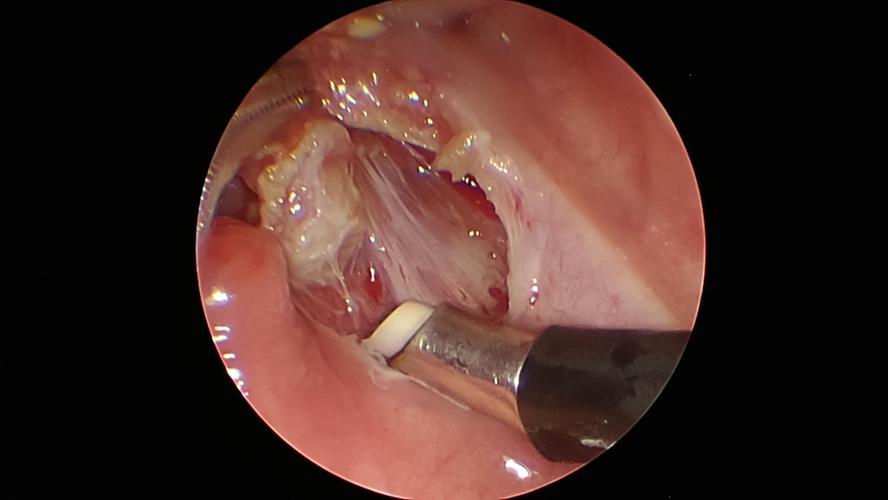

双扁桃体低温等离子切除术